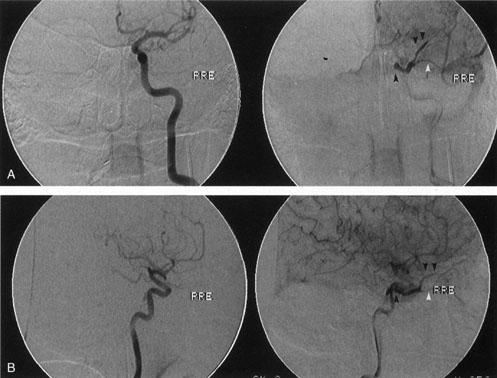

If the clinical suspicion is very high for an arteriovenous fistula, particularly if intervention is required, bilateral selective arteriography of the internal and external carotid arteries is indicated. This shows retrograde opacification of the cavernous sinus and the involved venous drainage system (Fig. 17). A difference in the ocular pulse amplitude (OPA; i.e., the difference between the maximum and minimum intraocular pressure during the cardiac cycle) between a patient's two eyes of more than 1.6 mm Hg may be useful to identify patients with either direct or indirect arteriovenous fistulas.124 This is performed by instilling a topical anesthetic drop into each eye, instructing the patient to look at the 20/400 “E” on a projected Snellen chart, and placing a pneumotonometer tip on the central cornea for 10 to 15 seconds. The difference in OPA between the two eyes then is calculated from the intraocular pressure curves. Ultrasound, CT, and MRI are neither sensitive nor specific. A-scan orbital ultrasonography and Doppler illustrate venous distention and dynamic flow. Color Doppler ultrasonography shows enlargement and arterialization of the venous flow (blood flow reversal), as well as enlarged extraocular muscles and may be useful in monitoring the clinical course of arteriovenous fistulas.109,125 Reversal of flow in the superior ophthalmic vein is not pathognomonic for arteriovenous fistula: It also has been described in carotid sinus thrombophlebitis, orbital apex tumors, and in normal persons.126 Computed tomography demonstrates enlargement of the superior ophthalmic vein and frequently enlargement of the extraocular muscles proportional to the degree of shunting (Fig. 18). There may be CT evidence of venous thrombosis in the form of a nonenhancing defect in the lumen of the superior ophthalmic vein or cavernous sinus. Magnetic resonance angiography (MRA) also may be used to evaluate these lesions, but false-negative results can occur.109

Fig. 17. Left internal carotid angiogram. The internal carotid artery within the cavernous sinus is seen in anteroposterior projection as a dark circle (A) and in lateral projection as an S-shaped structure (B). The fistula (black arrow) in this patient drained anteriorly into the superior ophthalmic vein (double arrow) and inferior ophthalmic vein (white arrow). In the absence of a history of trauma, the presumed etiology of the fistula in this patient was rupture of a preexisting intracavernous aneurysm.